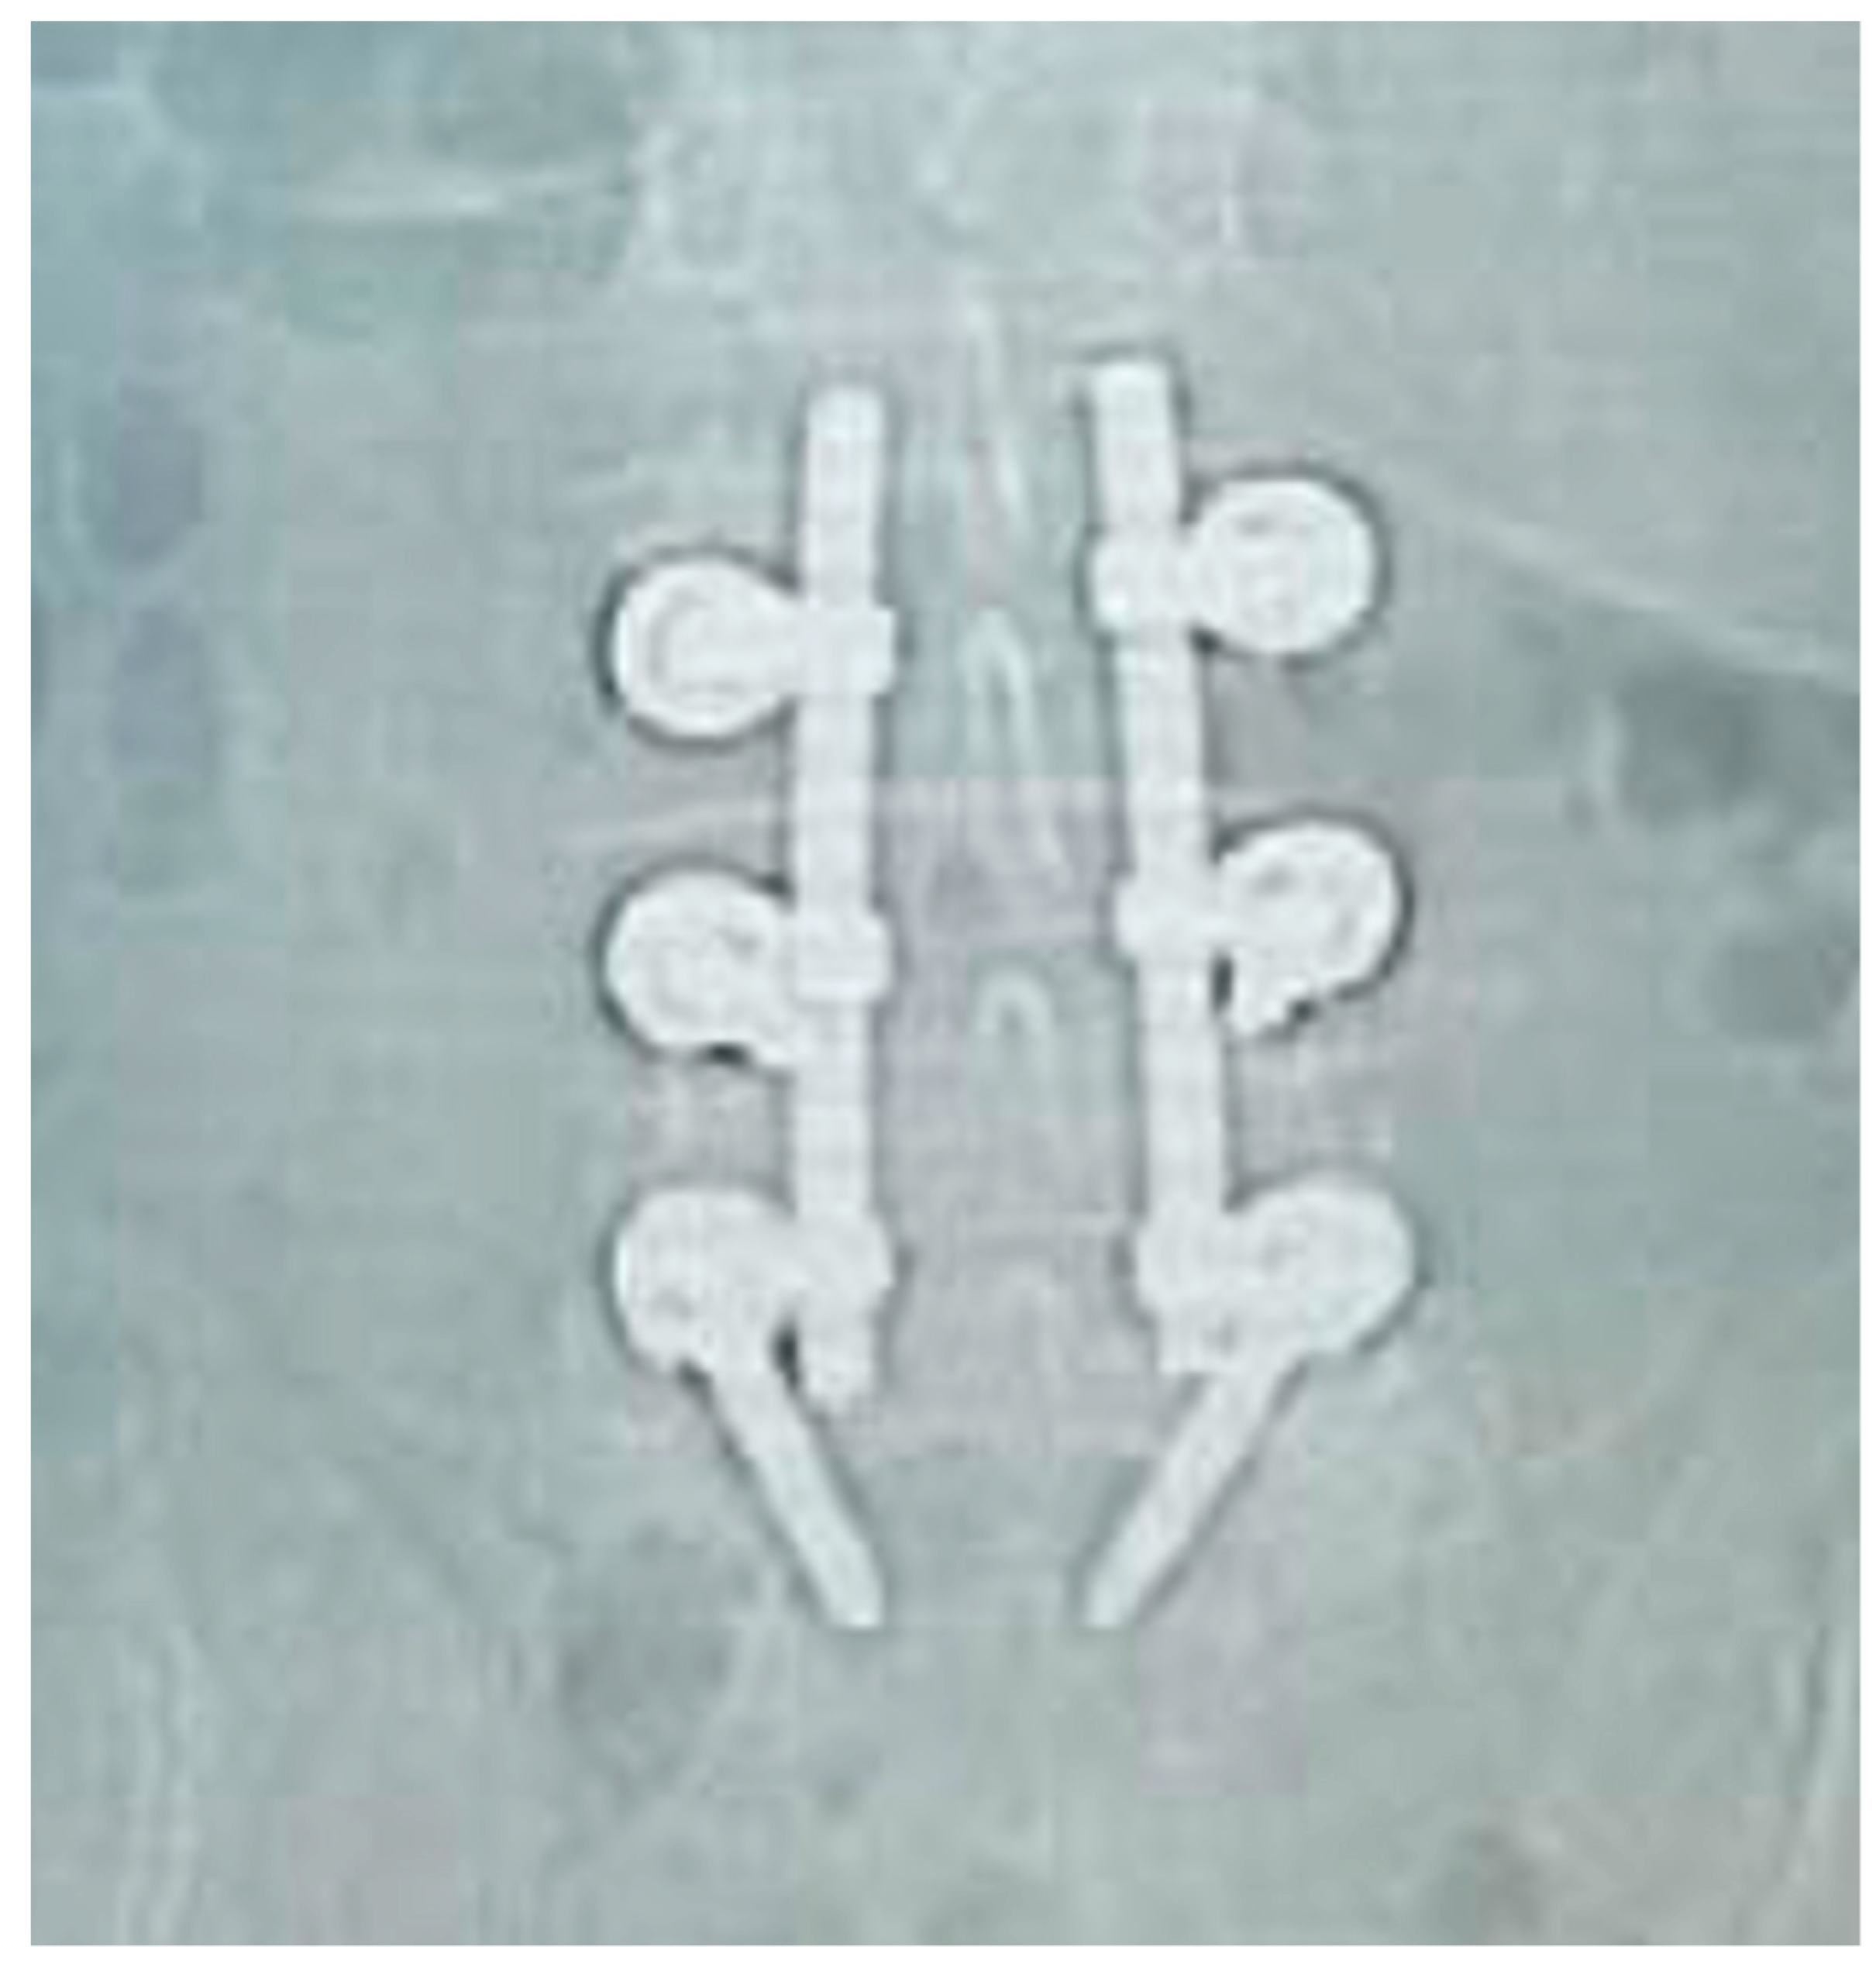

Figure 6, Figure 7, Figure 8 and Figure 9 show examples of pre- and post-operative X-ray shots.

Figure 8. Post-operative sagittal X-ray check—patient code: 5BML4L501.